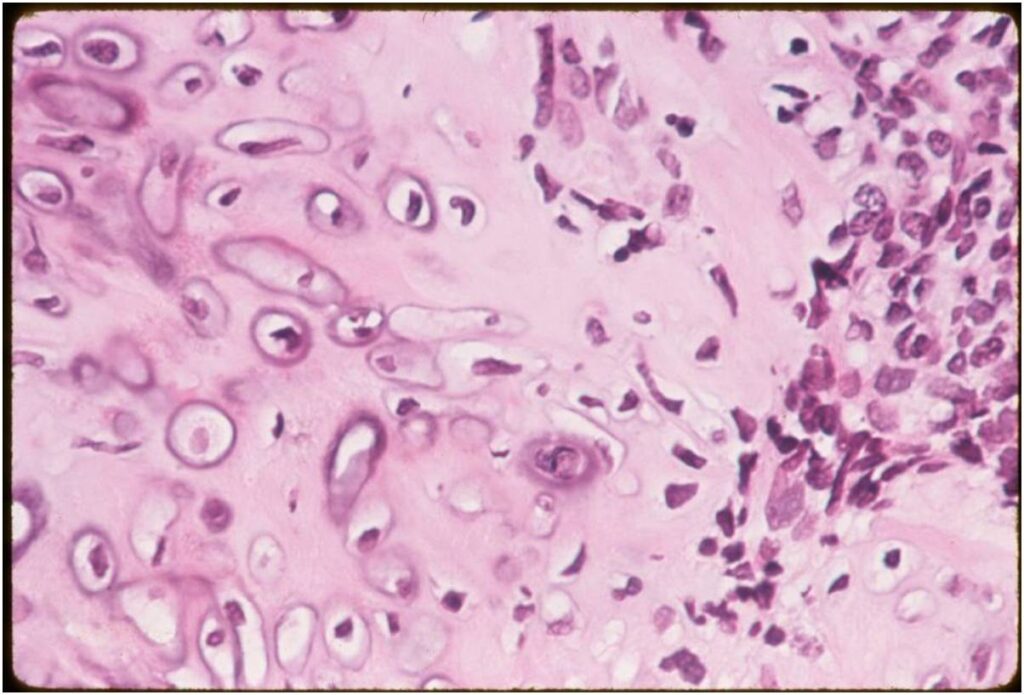

- Low grade islands of cartilage scattered throughout the mesenchymal cells

- Usually only a small part of lesion

- Cytologically low grade

- Usually sharply demarcated from surrounding stroma

- Stain S-100 positive

- Cells within cartilage

- Tend to have round or ovoid nuclei

- Lacunae are poorly formed

- May contain islands of collagen resembling osteoid